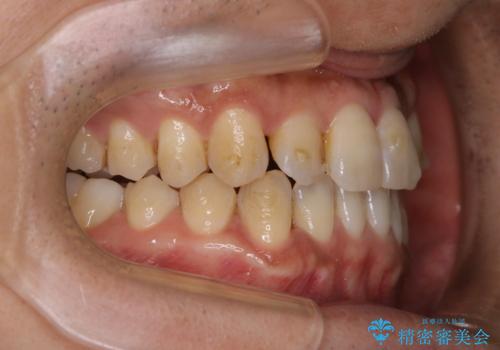

- インビザラインによるマウスピース矯正中に歯の黄ばみ・ステインが気になるとのことでした。PMTC60分コースを行いました。

PMTCは30分コース・60分コースがあります。

30分コースでは主に前歯をメインに行います。

60分コースでは全体的に行います。

お口の状態、ご希望に合わせて当日担当の歯科衛生士とご相談してから行うことが可能です。

※着色や歯石の量、お口の状態により60分コースでも全ての汚れを除去することができない場合もあります。